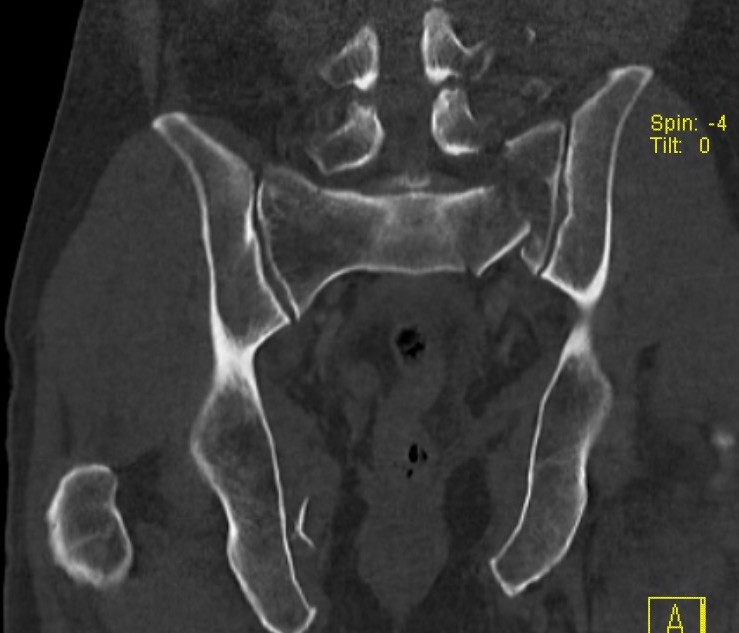

Posterior ring

- fracture sacrum / SI joint / ilium

Pathology

Anterior ring

- pubic symphysis disruption

- fracture of the superior and inferior pubic ramus